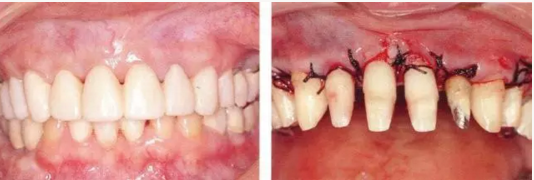

3.png

▲圖19-7

正畸治療完成時(shí)。

33.png

▲圖19-8,9

▲圖19-8  佩戴臨時(shí)修復(fù)體。即使在這個(gè)狀態(tài)下,依然有牙周袋殘留。

▲圖19-9  完成牙周外科治療后的狀態(tài)。

333.png

▲圖19-10,11

▲圖19-10  牙周外科治療后3周的狀態(tài)。從照片可見牙周袋的去除量。

▲圖19-11  數(shù)月以后,對(duì)臨時(shí)修復(fù)體進(jìn)行修整后的狀態(tài)。